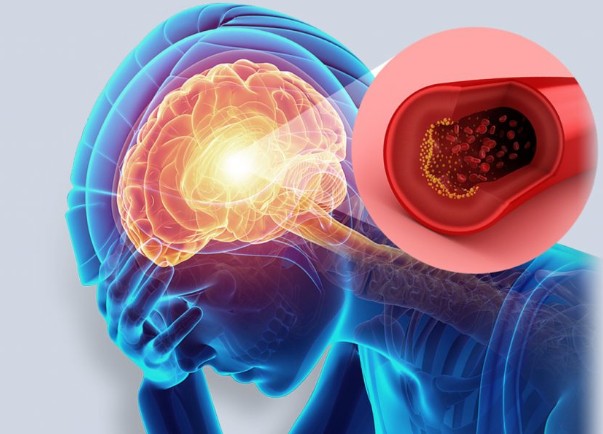

오늘은 많은 분들이 두려워하는 질환, 뇌경색의 초기 증상에 대해 이야기하려 합니다. 뇌경색은 뇌혈관이 막혀 뇌 조직이 손상되는 질환으로, 치료 시기를 놓치면 영구적인 장애를 남기거나 생명을 위협할 수 있습니다.

뇌경색은 뇌의 어느 부위가 손상되었는지에 따라 증상이 다르게 나타납니다. 증상이 한쪽 신체에 집중되어 나타나는 것이 특징이며, 증상이 나타났다가 24시간 내에 사라지는 경우(일과성 허혈 발작)도 있지만, 이는 뇌경색의 전조 증상이므로 반드시 병원을 찾아야 합니다. 다음은 뇌경색 환자들이 흔히 겪는 10가지 주요 초기 증상입니다.

- 즉시 119에 신고: 위와 같은 증상이 하나라도 나타나면 즉시 119에 신고하고 응급실을 방문해야 합니다. 증상 발생 후 4.5시간 이내에 혈전 용해제를 투여하면 후유증을 최소화할 수 있습니다.